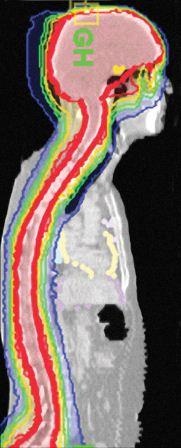

Während „herkömmliche" Bestrahlungsgeräte oft mit einem breiten Strahlenbündel arbeiten, das aus nur wenigen Winkeln um den Patienten geführt wird, ermöglicht der im Ring-Gantry integrierte Linearbeschleuniger die kontinuierliche, helikale Bestrahlung aus einer Vielzahl verschiedener Winkel. Dabei rotiert der Linearbeschleuniger spiralförmig um den Patienten, während dieser auf der Behandlungsliege durch das ringförmige

Bestrahlungsgerät bewegt wird. So können nicht nur mehrere Tumoren gleichzeitig an verschiedenen Stellen im Körper in einem einzigen Bestrahlungsfeld und während jeweils einer Sitzung bestrahlt werden. Es ist auch möglich, lange Bestrahlungsfelder (z.B. kraniospinale Behandlungen) in einem einzigen Durchschub zu bestrahlen. Eine größere Anzahl von Winkeln und eine präzise Modulation der Dosisverteilung führen zu einer exakt auf den jeweiligen Tumor abgestimmten Bestrahlung. So wird gesundes Gewebe maximal geschont.

Mit dem neuen System können zum einen die häufigen Indikationen der Strahlentherapie, wie Prostata- oder Brusttumoren, effektiv behandelt werden. Aber das TomoTherapy-System eignet sich auch besonders für Behandlungen, die bisher als kompliziert galten, wie schwierig lokalisierte Tumoren oder ausgedehnte Zielvolumen. Ein Beispiel hierfür sind Kopf-Hals-Karzinome, die an wichtige Strukturen wie Rückenmark, Ösophagus oder Speicheldrüsen angrenzen. Ein weiteres Beispiel ist die Ganzkörperbestrahlung z.B. bei Knochenmarktransplantationen („total marrow irradiation", TMI): Herkömmlicherweise führt eine solche Behandlung bei Patienten oft zu starker Übelkeit. Das TomoTherapy-System ermöglicht durch die voll-integrierte Planungs-, Bildgebungs- und Bestrahlungstechnologie die genaue Bestrahlung von krankhaft veränderten Strukturen mit einer hohen Strahlendosis bei größtmöglicher Aussparung wichtiger Organe.